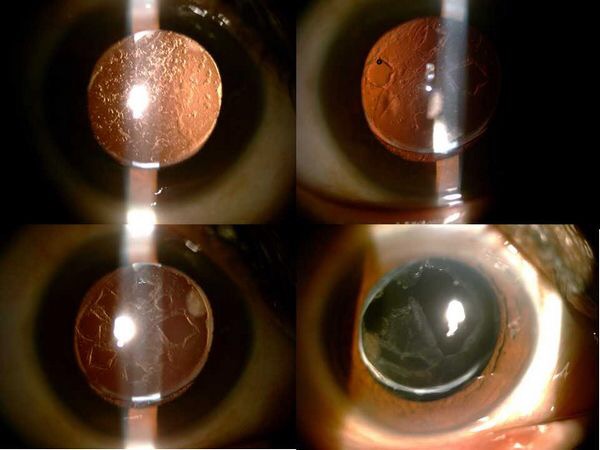

A:飛蠅症又稱飛蚊症和玻璃體混濁,是指玻璃體內出現不透明體,造成患者視物出現模糊。人出生時玻璃體呈凝膠狀態,是重要的屈光介質,正常的玻璃體隨著年齡逐漸出現液化,從而導致玻璃體混濁。此外,一切玻璃體混濁是由於病理原因所導致,例如玻璃體出血、葡萄……

A:眼前出現飛蚊的症狀往往是因為玻璃體發生了液化、變性和混濁,通常情況下玻璃體的混濁,比較多見於近視眼的人和年歲比較大的中老年人,還要特別重視的一個問題是當眼底有病變發生的時候,也會出現玻璃體的混濁、玻璃體混濁的加重,這時候眼前飛蚊的症狀需要做……

A:年輕人飛蚊症可由以下常見原因所導致:1、高度近視:通常是指600度以上的近視,在近視的發展過程中玻璃體會逐漸液化,從而表現為飛蚊症。如果除了有飛蚊症的感覺,還伴有眼前的異常散光感,或者短時間內飛蚊不斷增加,年輕人需要到醫院進行眼底檢查,防……

A:年輕人眼睛出現飛蚊症,根據病因不同治療也有所不同,常見病因如下:1、高度近視所引起:通常是指600度以上的近視,在近視的發展過程中,玻璃體逐漸液化出現飛蚊症。如果僅有飛蚊症的感覺,通常不需要進行特殊的治療,但是需要去醫院進行定期檢查,防止……